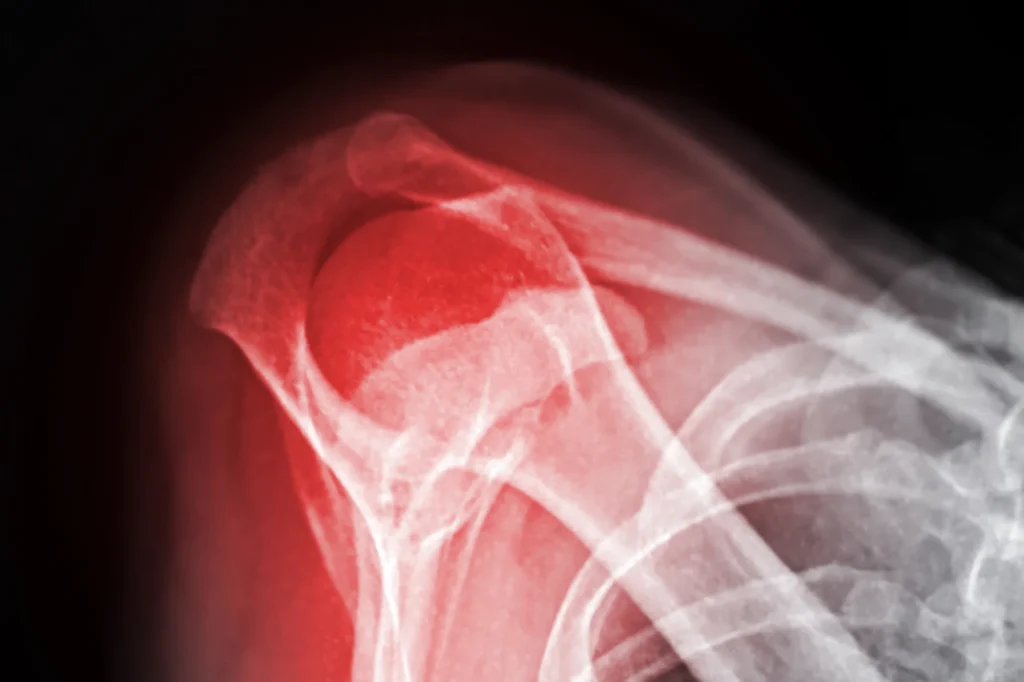

The shoulder joint represents one of the most mobile joints in the human body, allowing us to reach in virtually any direction. However, this mobility comes with less inherent bony stability compared to other joints, making the shoulder vulnerable to various injuries, including fractures. A shoulder fracture refers to a break in any of the three bones that form the shoulder complex. The proximal humerus is one of the most commonly fractured bones in the shoulder region, particularly in older adults. The clavicle is also frequently fractured, particularly in children, adolescents, and younger adults. Scapular fractures, while less common, typically result from high-energy trauma.

Shoulder fractured

Fractures can be classified in several ways. A closed fracture means the bone is broken but the skin remains intact, while an open fracture involves the broken bone piercing through the skin. Fractures can also be displaced, where fragments have moved out of alignment, or non-displaced, where pieces remain relatively close to their original position.